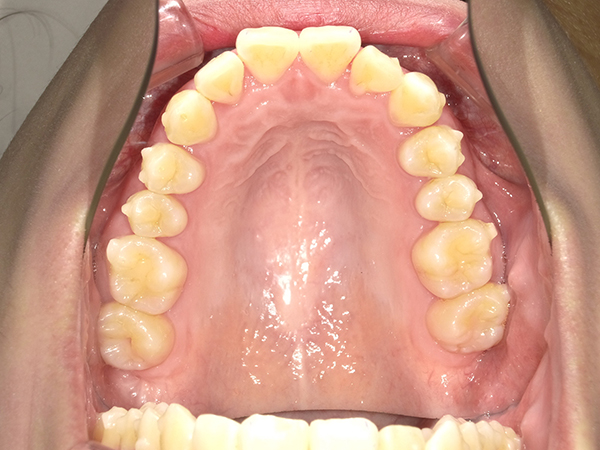

順調に矯正が進んでいき、2020年11月の時点でここまで並んできました。

前回の記事に載せていた、上の歯の隙間も見事に閉じて綺麗になってきました。

一番気になっている、上下 前歯たちの整列が始まります|( ̄3 ̄)|